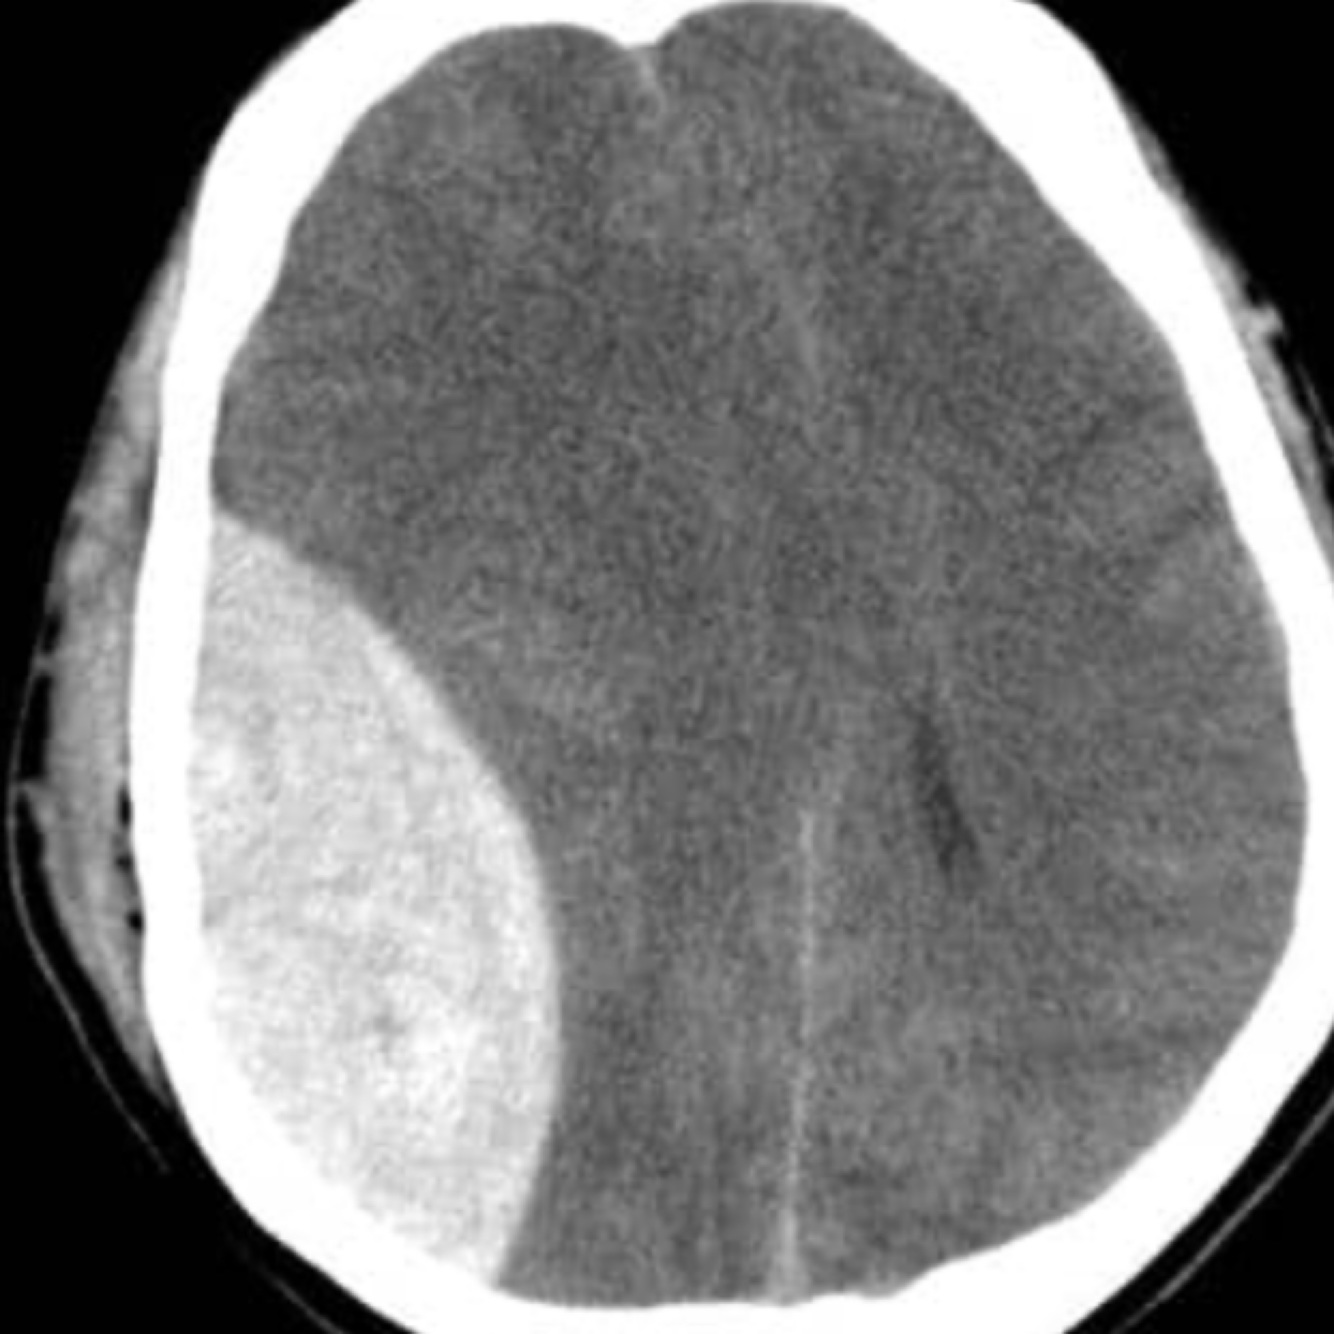

Extradural haemorrhage

This is a haemorrhage between the skull and dura mater of the meninges.

Commonly caused by trauma to the pterion, with subsequent tearing of the middle meningeal artery,

patients present with acute severe headache, contralateral hemiplegia, and a rapid deterioration in GCS following a lucid period.

On CT, a biconvex hematoma is diagnostic.

This occurs as the haemorrhage stops expanding at the sutures of the skull, where the dura meets the skull, causing the haemorrhage to expand towards the brain.

Neurosurgical

intervention is usually needed.

Haematoma expansion limited by sutures of the skull so expands towards the brain giving characteristic biconvex hyper dense area

Extradural haemorrhage is usually caused by rupture of the middle meningeal artery in the temporo-parietal region. It can be associated with a fracture of the temporal bone. It occurs between the skull and dura mater. On a CT scan they have a bi-convex shape and are limited by the cranial sutures (they can’t cross over the sutures).